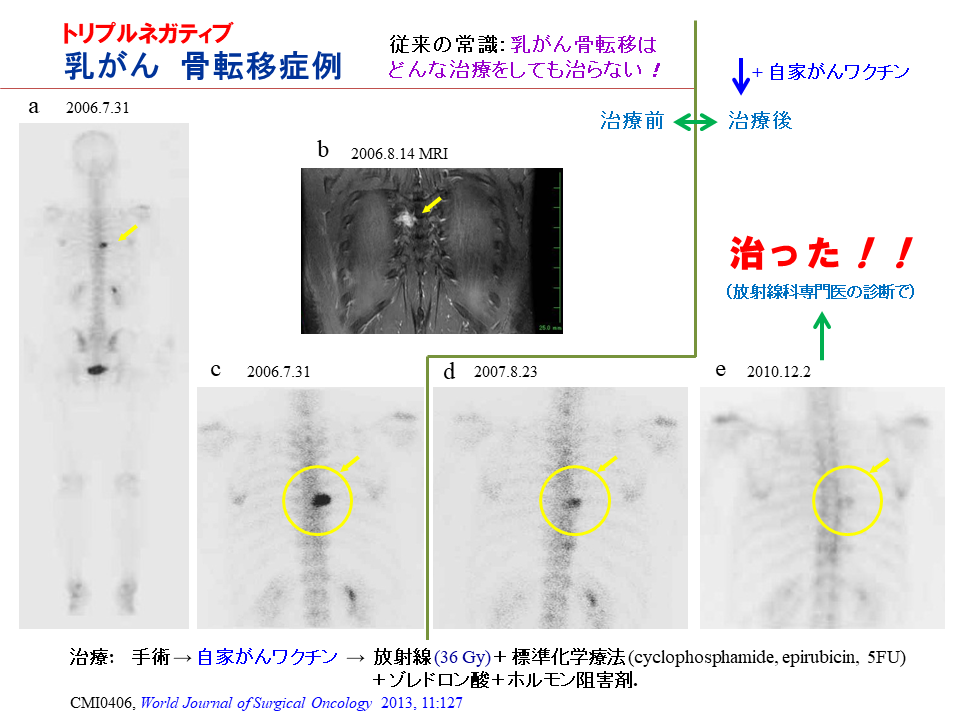

がん種ごとの症例 がん治療の専門医も驚いた症例の数々 臨床効果

がん種ごとの症例 乳がん 臨床効果 がん免疫療法 自家がんワクチン